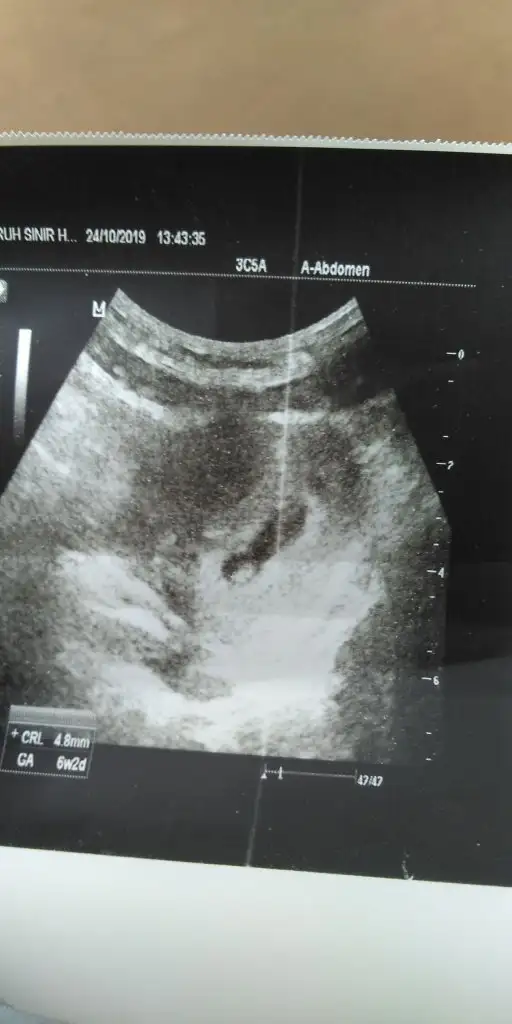

Kizlar bebegim gorundu 6+2 imiş bebegin kalbini duydugu fakat makinasi eski oldgundan dolayi sesinibana veremedgni soledi doktor benim icim icime sığmıyor acaba siz bu bebegin kalbini gorebiliyomusunuz sizinde basiniza ole geldmi

4 senem21 Cok biliyorsun şekerim 🙈 Kayıtlı Üye 24 Haziran 2019 211 55 28 28 24 Ekim 2019 Konu Sahibi Konu Sahibi 4 senem21 #2 4 senem21 .!.: Kizlar bebegim gorundu 6+2 imiş bebegin kalbini duydugu fakat makinasi eski oldgundan dolayi sesinibana veremedgni soledi doktor benim icim icime sığmıyor acaba siz bu bebegin kalbini gorebiliyomusunuz ☺☺☺☺☺ sizinde basiniza ole geldmi Genişletmek için tıkla... Eklentiler IMG-20191024-WA0009.webp 21,9 KB · Görüntüleme: 135

Ozgelin 🧿 Anneler Kulübü Kayıtlı Üye 4 Haziran 2018 885 1.135 113 24 Ekim 2019 Konu Sahibi Konu Sahibi 4 senem21 #3 Kalbi atıyomuş ya çok şükür.. bizde ilk attığını gördük ama duymadık çok minik diye..diğer gidişimizde güppp güpppp güppp güp

Kalbi atıyomuş ya çok şükür.. bizde ilk attığını gördük ama duymadık çok minik diye..diğer gidişimizde güppp güpppp güppp güp

4 senem21 Cok biliyorsun şekerim 🙈 Kayıtlı Üye 24 Haziran 2019 211 55 28 28 24 Ekim 2019 Konu Sahibi Konu Sahibi 4 senem21 #4 Ozgegelin .!.: Kalbi atıyomuş ya çok şükür.. bizde ilk attığını gördük ama duymadık çok minik diye..diğer gidişimizde güppp güpppp güppp güp Genişletmek için tıkla... Biz bu resme bakinca kalbi gorebilirmiyiz peki

Ozgelin 🧿 Anneler Kulübü Kayıtlı Üye 4 Haziran 2018 885 1.135 113 24 Ekim 2019 Konu Sahibi Konu Sahibi 4 senem21 #5 Kameraya çekseydin görürdün belki orda nokta kadar bişi yanıp sönüyo gibi oluyor